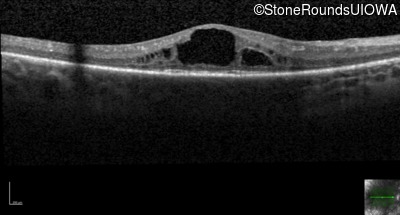

Optical Coherence Tomography - Right - 20/60 -1

Exemplar / OCT Stack